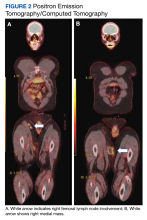

figure 2

Special immunohistochemical staining showed most of the lymphocytes were CD20 positive B-cells with a minority of CD3 positive T-cells. Histiocytes were CD163 positive and CD68 positive with patchy reactivity for S100 protein. The plasma cells were CD138 positive. There were > 125 IgG4-positive plasma cells present in a single high-powered field and the overall IgG4:IgG plasma cell ratio was > 40%. Pertinent imaging included a whole-body positron emission tomography/computed tomography (PET/CT) hypermetabolic activity scan of a small right femoral lymph node (9 mm) and nearby medial right femoral lymph node (13 mm) (Figure 2A). A well-defined mass in the medial aspect of the right thigh (2.5 cm x 3.2 cm x 3.9 cm) and a cutaneous/subcutaneous lesion of the anterior medial aspect of the proximal right thigh superior to the mass (2.9 cm) were also evident on imaging (Figure 2B). Each area of hypermetabolic activity had decreased in size and activity when compared to a previous PET/CT obtained 1 month earlier. There was no evidence of skeletal malignancy. A physical examination did not reveal any other soft tissue masses, palpable lymphadenopathy, or areas of skin involvement. Given the patient’s reassuring imaging findings and a lack of any new physical examination findings, no systemic therapy was initiated, and following shared decision making, the patient agreed to a period of watchful waiting.